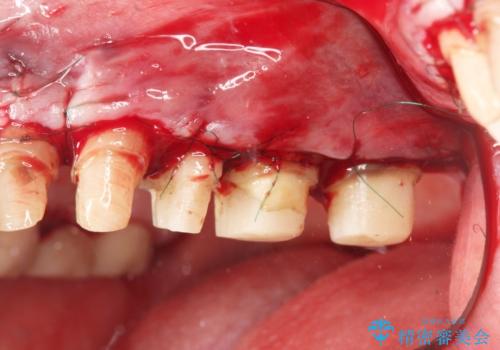

歯周外科手術をおこなったことでフェルールも獲得でき、破折リスクをより抑えることにも成功しています。

外科処置の注意事項(リスク・副作用など)

- 外科手術のため、術後に出血、痛みや腫れ、違和感を伴います